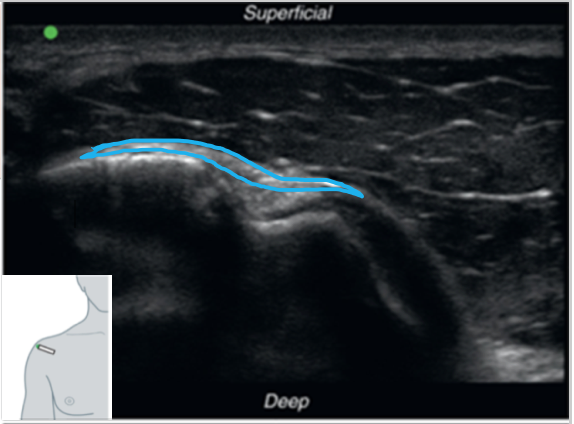

FASE2Q18